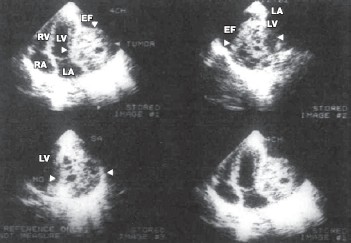

Живые кисты наполнены прозрачной жидкостью, имеют сферическую или овальную форму и отдельные дочерние пузыри, окруженные более тонкой хитиновой оболочкой. Они могут достигать больших размеров и тогда (если толщина хитиновой оболочки находится в пределах разрешающей способности используемого ультразвукового прибора) в реальном времени видна ундулирующая мембрана — стенка дочернего пузыря, что мы обнаружили всего у одного из 6 пациентов с эхинококковой кистой сердца. У 5 пациентов локализация эхинококковой кисты была интракардиальной: у одного пациента с поливисцеральным эхинококкозом обнаружено солидное округлое образование повышенной эхогенности в области верхушки ЛЖ, у другого — в полости правого желудочка, исходящее из межжелудочковой перегородки (МЖП), остальные — интрамиокардиальной локализации. И лишь у одной пациентки киста исходила из висцерального листка перикарда на срединноапикальном уровне задней стенки ЛЖ и была размерами 4,5х3,6 см (рис. 2).

Рисунок 2. Двухмерная ЭхоКГ пациентки К., 60 лет.

Эхинококковая киста перикарда ЛЖ. Здесь и на рис. 4, 5: LV, ЛЖ — левый желудочек; LA — левое предсердие; APEX — верхушка сердца; CIST — киста.

При трансторакальной ЭхоКГ отмечены увеличение правых отделов сердца и овальной формы образование размером 4,4х3,2 см, содержащее жидкость и тонкую перемычку, видимую при получении изображения в реальном времени и исходящее из правой части МЖП, занимающее большую часть полости правого желудочка (рис. 3).

Рисунок 3.Двухмерная ЭхоКГ пациентки Б., 9 лет.

Эхинококковая киста в полости правого желудочка, исходящая из МЖП. 1 - полость правого желудочка.

Опухолевые кисты возникают в случае, если растущая ткань опухоли формирует однокамерные или чаще многокамерные полости. К разряду опухолевых кист относятся обнаруженные нами при двухмерной ЭхоКГ множественные мелкие и округлые эхонегативные включения в обширном объемном образовании (размерами 7х7,5 см), локализующемся в области боковых стенок ЛЖ и левого предсердия (рис. 4). Существующее образование изменяло геометрию полости ЛЖ и левого предсердия и сопровождалось массивным перикардиальным выпотом (гемоперикардом). По данным импульсноволновой допплер-ЭхоКГ, ангиосаркома миокарда препятствовала активному расслаблению миокарда и приводила к глобальной диастолической дисфункции ЛЖ I типа.

Рисунок 4. Двухмерная ЭхоКГ, выполненная из различных акустических "окон", пациентка К., 29 лет.

Диагноз: ангиосаркома миокарда (указана стрелками). RV— правый желудочек; RA — правое предсердие; EF — перикардиальный выпот.